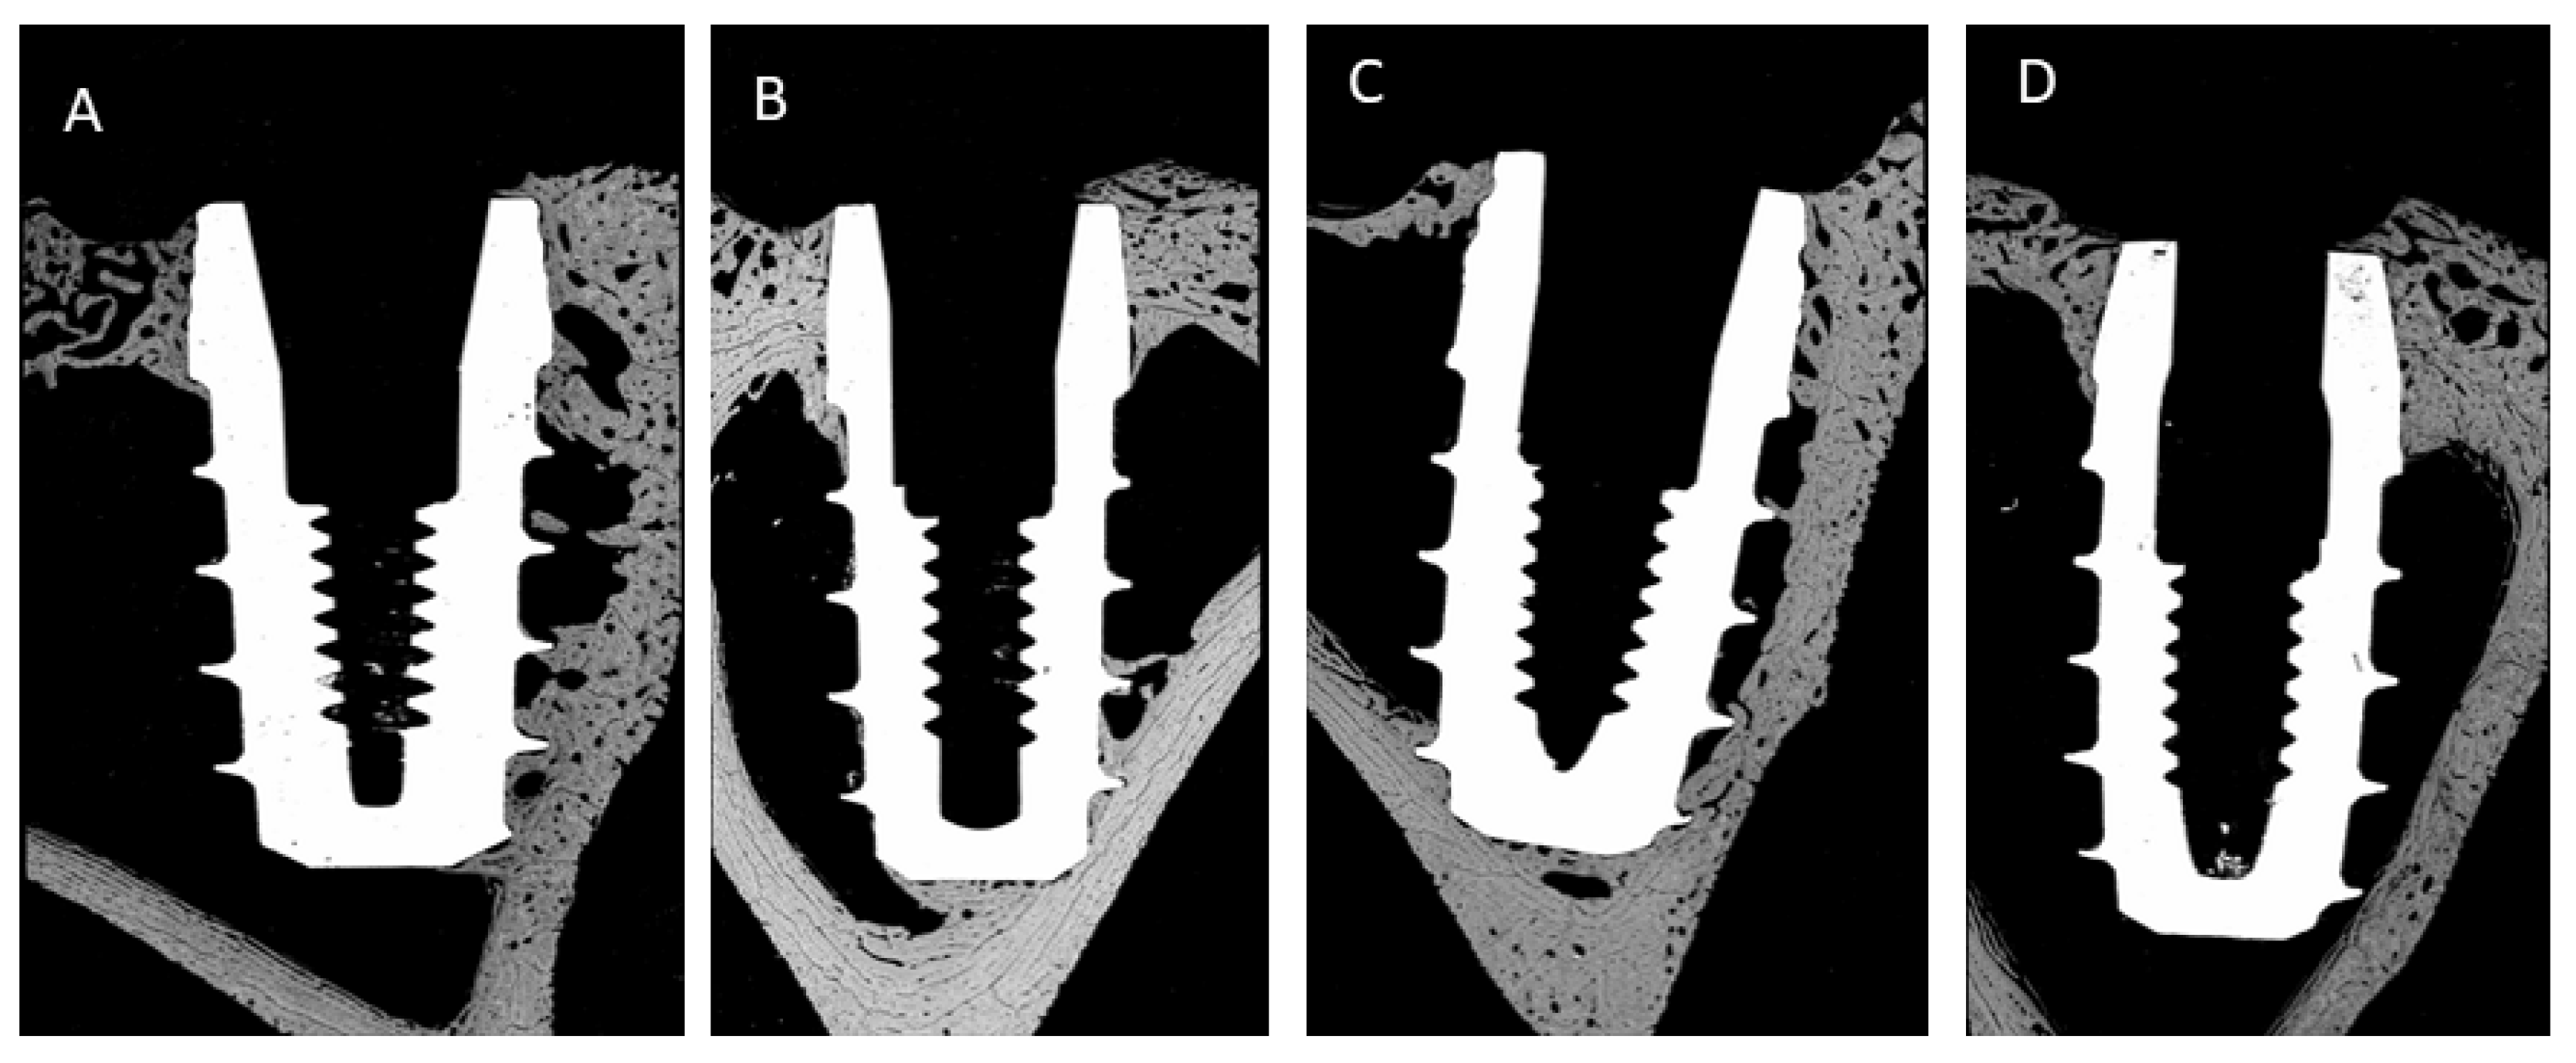

| BIC | 3 Weeks | 6 Weeks |

| Above 0.5 mm | 12% ± 3% | 19% ± 5% |

| Bone level | 18% ± 6% | 25% ± 9% |

| Below 0.5 mm | 29% ± 4% * | 39% ± 9% * |

| BAT | 3 Weeks | 6 Weeks |

| Above 0.5 mm | 16% ± 4% | 27% ± 8% |

| Bone level | 26% ± 6% | 35% ± 9% |

| Below 0.5 mm | 35% ± 5% * | 48% ± 5% * |

| ROI | 3 Weeks | 6 Weeks |

| Above 0.5 mm | 20 ± 5% | 26% ±4% |

| Bone level | 25% ± 6% | 32% ± 5% |

| Below 0.5 mm | 29% ± 8% * | 45% ± 8% * |